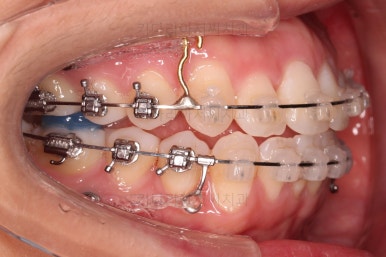

이번 환자분이 선택하신 장치는 데이몬 클리어라고 하는 자가결찰 세라믹 장치인데요.

데이몬 클리어는 현재 사용되는 세라믹 장치 중에 가장 심미성이 뛰어난 장치입니다.

흔히 세라믹 장치로 많이 아시는 클리피씨, 엠파워 클리어 등을 철사를 잡아주는 캡이 메탈로 되어 있어 유심히 관찰하면 메탈 부분이 있는 반면에 데이몬 클리어는 캡 자체도 세라믹으로 되어있어 심미성이 좋습니다.

다만, 통 바디 형태의 세라믹으로 되어있다 보니 강도 증가를 위해서 부피가 약간 더 커진 단점은 있습니다.

상하좌우 총 4개의 미니스크류를 이용해서 치열을 뒤로 당겨줍니다.

중간평가를 하면서 환자분과 가능한 수준/원하는 수준을 잘 조율해 가면서 입매를 정해갑니다.